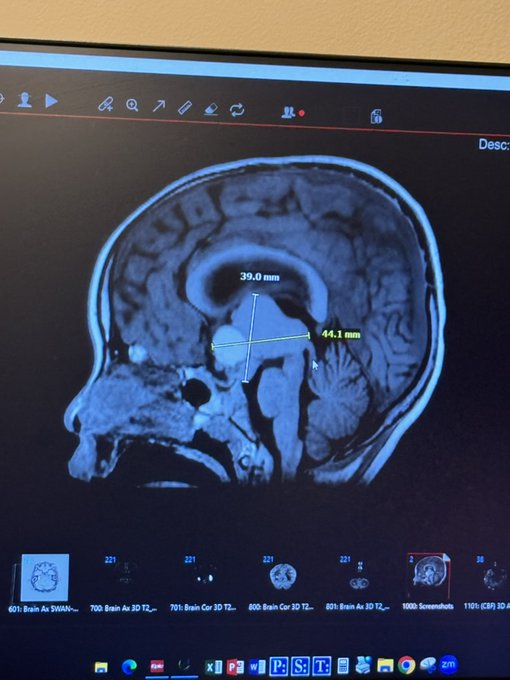

在9/23日,米拉被诊断出患有一种罕见的脑瘤,名为颅咽管瘤。

虽然良性,但它位于大脑极其危险的区域,并且与所有可存活的脑肿瘤中与生活质量最差的结果相关。